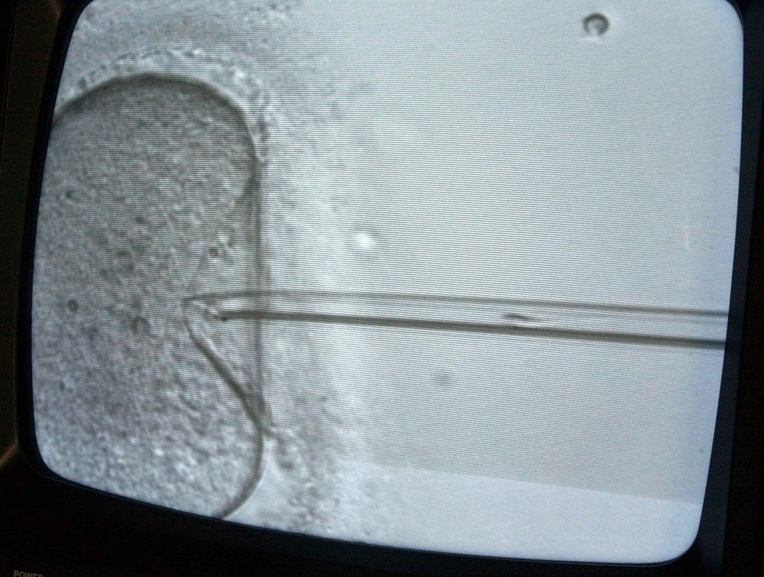

Los Angeles, Etats-Unis | AFP | jeudi 10/07/2019 - Un couple californien a engagé mercredi des poursuites en justice à l'encontre d'une clinique pratiquant des fécondations in-vitro, après qu'une dramatique erreur a conduit un autre couple à porter et mettre au monde leur enfant.